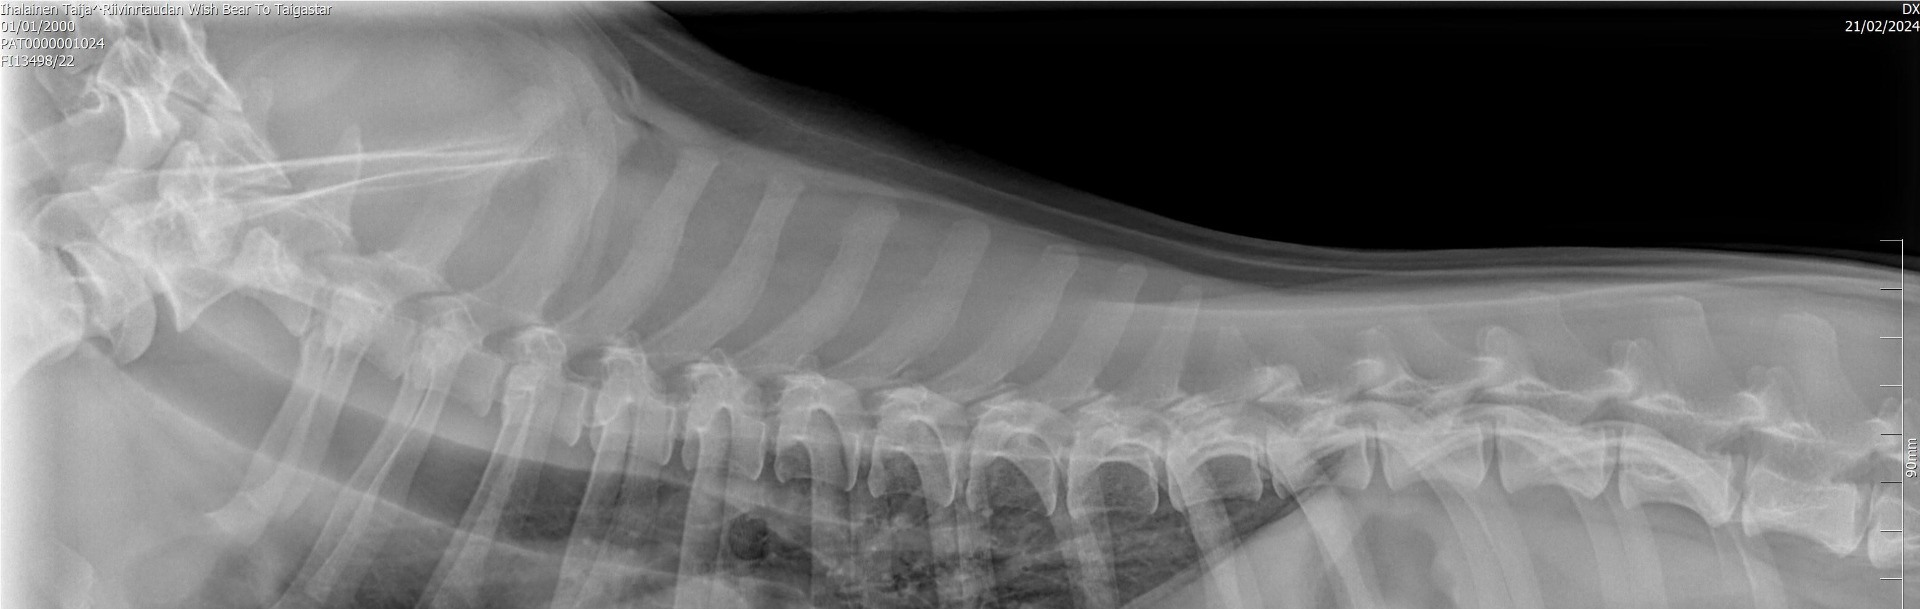

Kondrodystrofia (CDDY/IVDD) ja kondrodysplasia (CDPA)